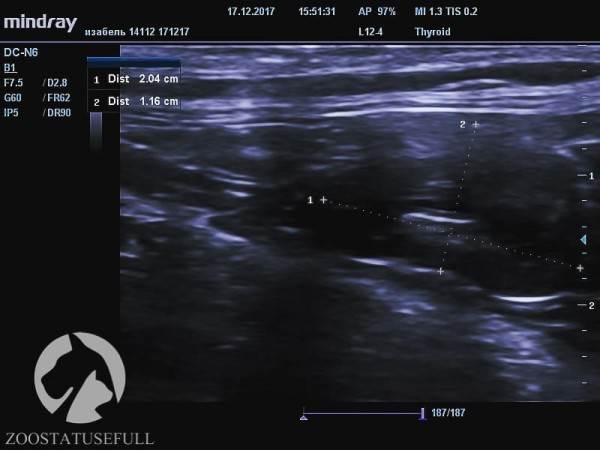

Здоровая почка кошки Изабель (обратите внимание на размер, указан в см)

Больная почка кошки Изабель

Но самое главное — воспалительный процесс, возникший в мочевыделительной системе на фоне «неотжимания» привёл к заболеванию, а потом и к «гибели» одной из почек. На снимках можно увидеть разницу между функционирующей почкой и нефункционирующей.